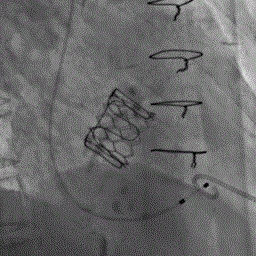

术前经详尽评估患者病情,通过CT重建测量瓣环直径、左室流出道面积。结合之前外科换瓣手术入路,最终决定对该病例采用经心尖途径行二尖瓣“瓣中瓣”手术。既往植入27# CE BP猪瓣,测量支架内径23mm,选用25# Renato球扩式瓣中瓣。手术过程顺利,最终瓣中瓣植入位置理想,功能表现出色,左室造影及经食道超声观察无明显瓣中及瓣周反流。瓣中瓣植入后观察左房峰值压明显下降,二尖瓣平均跨瓣压差降至1mmHg,左室流出道压差正常。

术前左室造影见大量反流 术后左室造影无反流

瓣中瓣释放